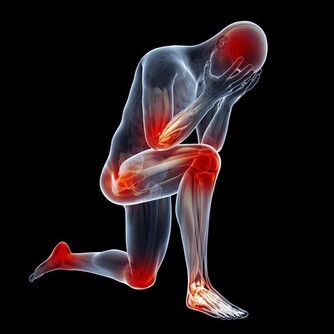

長年熬夜的人,無論男女,直接傷肝,日久傷腎,逐步造成身體氣血雙虧,每天照鏡子時會覺得臉色灰土一片。

許多精神不振的人,多有晚睡的習慣,這往往容易傷肝傷精傷膽。

這樣的人,眼睛往往也不好使,心情多抑鬱,快樂的時候不多(肺氣也受影響,長期得不到有效宣發的原因)。